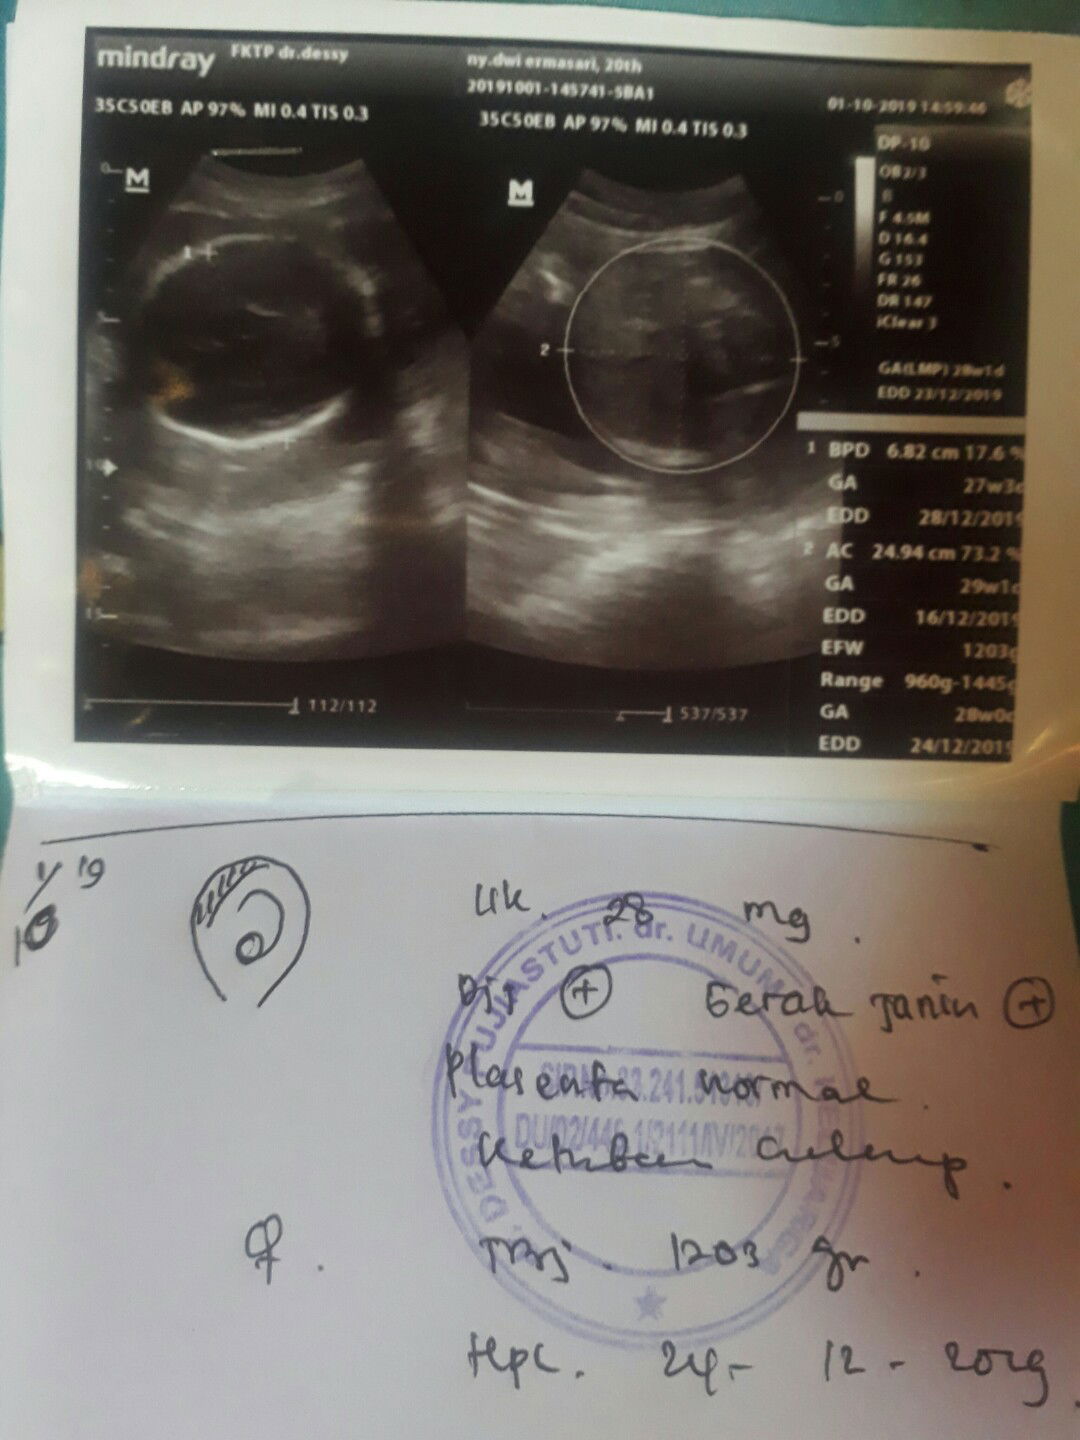

usg

Hay bun ini hasil usg ke 3 ku.. Uk 28 weeks.. Bb masih 1200 kira2 normal gk ya bun?